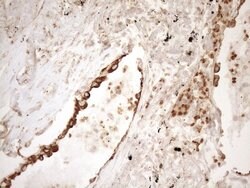

| Immunohistochemistry (Paraffin), Western Blot | |